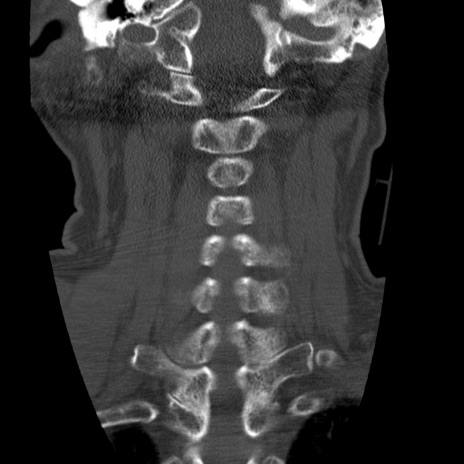

症例50 頚椎CT(冠状断像)

頚椎CT